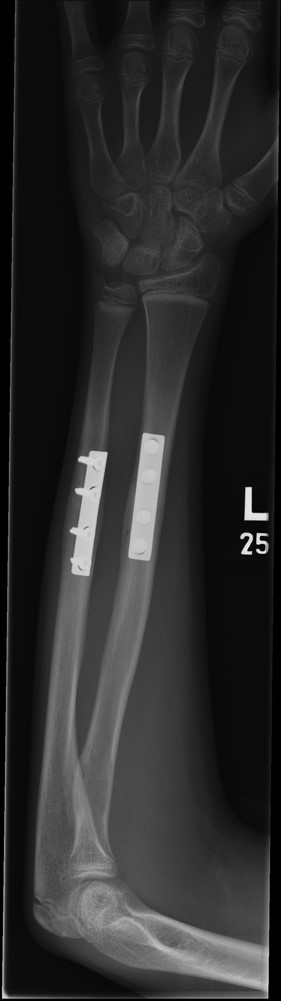

A 12-year-old male patient sustained a closed midshaft both-bone forearm fracture of their non-dominant arm from a fall on a trampoline (Figs 1 and 2). Anatomical reduction was achieved with a manipulation under anaesthesia (MUA), but it was noticed that there was a mechanical block to extension of the ring finger. The radius and ulna were therefore approached through separate incisions and it was discovered that the FDP was entrapped at the ulna fracture at the level of the musculotendinous junction. Following release the fingers regained a full range of motion and the patient went on to heal without further complication (Figs 3 and 4).

Pre-operative anteroposterior (AP) radiograph showing level of fracture at the junction of proximal two-thirds and distal one-third.